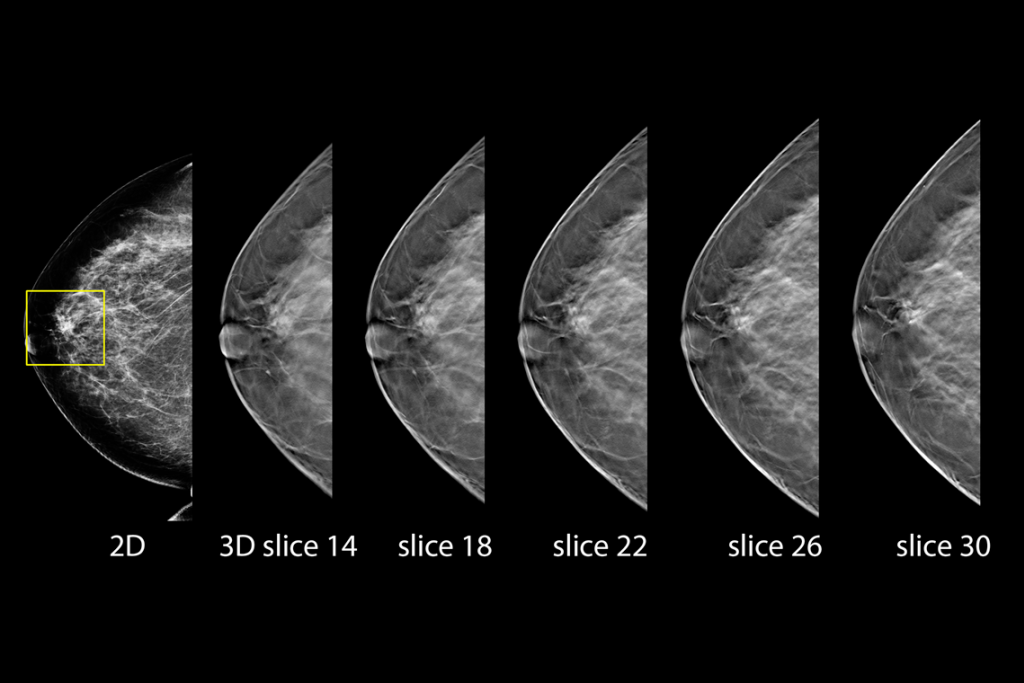

Klinische Aufnahmen einer Brustuntersuchung bei hohem Fettgewebeanteil